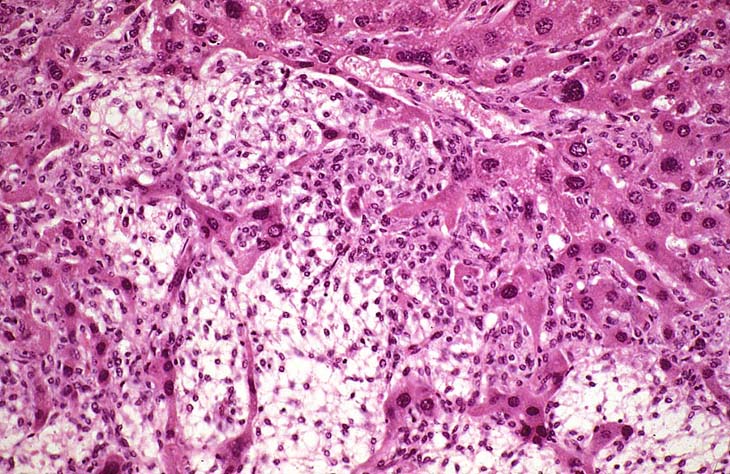

An Ito cell tumor that has replaced much of the normal hepatic parenchyma without distorting the normal contour of the liver; higher magnification shows fat-filled and stellate cells in the hepatic sinusoids.

The proliferating stellate cells have a myxomatous appearance in some areas and have caused atrophy of hepatic cords.